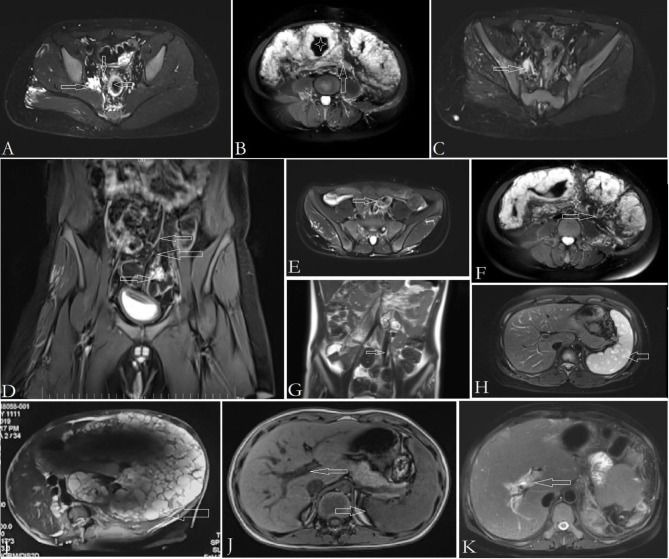

Fig. 4.

MRI findings in KTS with anorectal and anorectosigmoid VM. Panel A: Dilated, incompetent middle rectal vein (rightward arrow), perirectal VM (downward arrow), and thickening of rectal wall by VM involving (leftward arrow). Panel B: Sigmoid lumen became narrowed by thickening of the wall (asterisk). The mesentery of sigmoid colon become thickened and edematous (arrow). Panel C: Dilated, incompetent IIV (rightward arrow) is demonstrated. Typical fluid signal in the lumen is indicative of stagnation and/or reflux of blood. Panel D: Part of VM in rectosigmoid colon (rightward arrow) drains into the superior rectal vein (leftward arrows). Panel E and G: Ectatic and incompetent inferior mesenteric vein is identified (arrow). Heterogeneous signal in the lumen is indicative of blood stagnation, turbulent flow and reflux. Panel F: Dilation and tortuosity of the sigmoid vein in the mesentery (arrow). It drains into inferior mesenteric vein. Thickening and edema of the sigmoid mesentery also can be identified (asterisk). Panel H and I: Multiple cystic lymphatic malformations within the spleen (arrow). Splenectomy is indicated for massive splenomegaly (Panel I). Panel J: Main branches of portal vein become dilated (leftward arrow), and spleen enlarged (rightward arrow), which is suggestive of portal hypertension, although obstruction is not evident. Panel K: Main branches of portal vein become dilated and obstructed (arrow). Circumferential edema is notable. The spleen was resected because of portal hypertension and massive splenomegaly by lymphatic malformations

KTS is a complex low-flow vascular malformation with absence of arterial component. So basic magnetic resonance imaging (MRI) sequences is preferred to evaluate most of the findings in KTS [1, 3]. In KTS patients with gastrointestinal involvement, the findings on MRI sequences include thickening of the anorecto(sigmoid) colon by circumferential and intra-walled VM, edema and thickening of the affected mesentery, malformations and incompetency of IIV and IMV systems, dilation of mesenteric veins, and possible lymphatic malformation of spleen (Fig. 4). Dilation and/or occlusion of portal vein and branches also can be identified on MRI sequences (Fig. 4).

VM of pelvis and colon, and lymphatic malformation of spleen feature a typical fluid signal on T2-weighted MRI sequences [3] (Fig. 4). Incompetency of the involved veins features a higher fluid signal than that in normal veins on T2-weighted MRI sequences [2, 3] (Fig. 4). Dilation of these veins is an indication of the presence of reflux [2]. In our study, basic MRI sequences is highly sensitive to detect the IIV reflux in KTS with pelvis involvement; the sensitivity was as high as 97.56%2. Dilation and tortuousity of mesenteric veins in the affected area also can be demonstrated on MRI (Fig. 4). Additionally, phlebolith is charactered by local low signal within VM (Fig. 4).